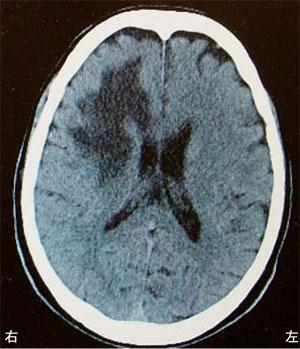

脳梗塞の発生部位によって出現する症状は異なります。この問題では、それぞれの部位における症状を正確に理解することが求められています。

右小脳半球では、右(同側)上下肢の運動失調が見られるため、この選択肢は誤りです。小脳半球の症状には、同側上下肢の運動失調や筋緊張の低下が含まれます。